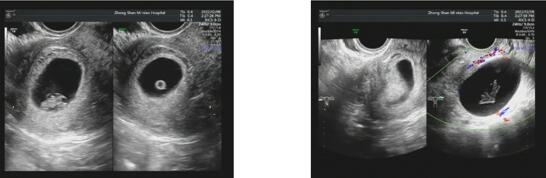

按照张宏展主任制定的拮抗剂方案,周期医生肖珊细心负责其促排治疗及卵泡监测的事宜。

经过努力的促排治疗,刘女士一共获卵4枚,冷冻2个优质卵裂胚。可喜可贺,终于算是有了优质的“种子”,这不就是离好孕希望更近一步了吗?

2022年11月,刘女士顺利复苏冷冻移植,一次验得好孕,成功圆了“二胎梦”!